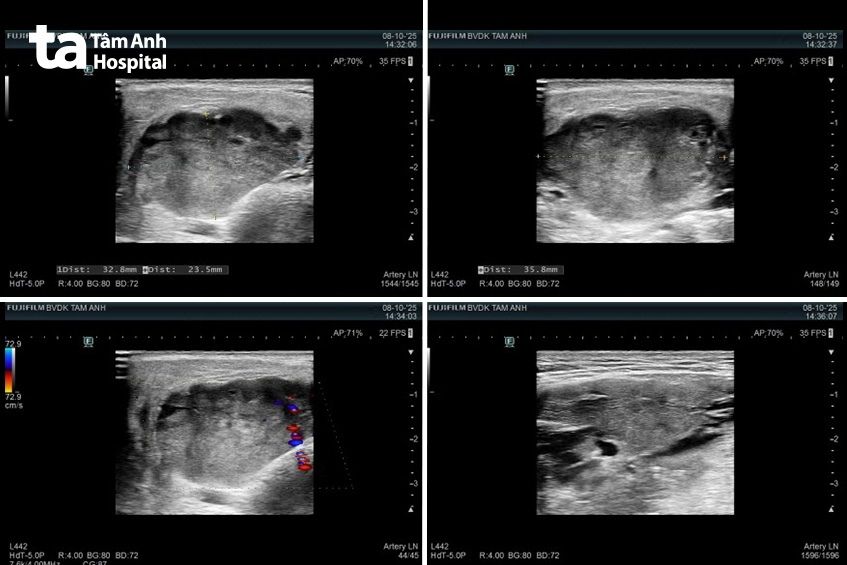

Kết quả chụp chiếu vùng mang tai và cổ cho thấy u tuyến mang tai trái kích thước 29×15 mm, ranh giới rõ, bờ cong đều, không vôi hóa. Các tuyến nước bọt khác và hạch vùng cổ bình thường, chưa ghi nhận dấu hiệu viêm hay di căn. Bác sĩ còn phát hiện một vài nhân nhỏ ở tuyến giáp hai bên, kích thước lớn nhất 22×13 mm, lành tính.